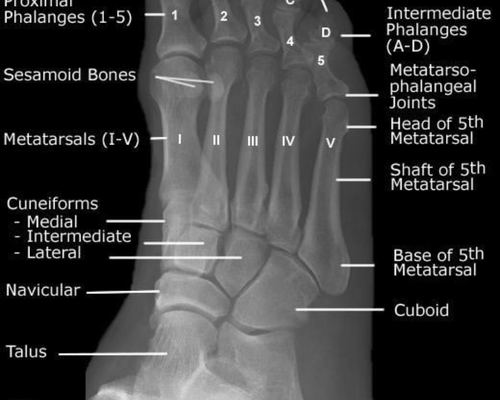

オステオパシー臨床報告その1女性/50代【症状】右足が痛い。ほぼ1日を通して痛みがあり、時間が経つにつれて痛みが大きくなる。右足全体にむくみと硬さがある。自身でさすったり、また触っただけでも...

オステオパシー臨床報告その7 右足の古傷 女性/30代【症状】慢性疲労と首肩の疲れで来店。首肩の疲れということで来店ですが、全身を順番に見ていくと、右足のすねに異様な硬さを感じる。聞くと、過...